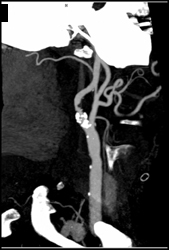

Carotid Artery Stenosis